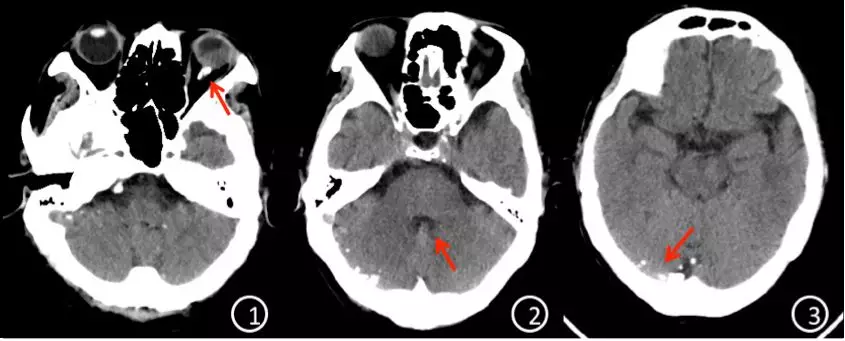

经上述治疗后,患者病情稳定,顺利出院,除左眼视力失明外,无其他神经功能缺失。复查头颅CT见颅内重水已明显减少,门诊随访(图4)。

图4. ①头颅CT平扫红色箭头提示眼眶内仍有重水残留;②四脑室已无重水蓄积;③仍有少量重水蓄积于枕叶蛛网膜下腔。